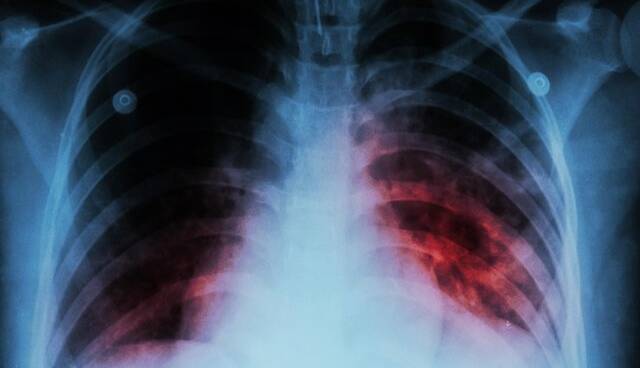

ایسنا/ رییس مرکز مدیریت بیماری‌های واگیر وزارت بهداشت با اشاره به وضعیت کنترل بیماری سل در ایران گفت: حتی اگر برآورد ۱۱ در ۱۰۰ هزار نفر را ملاک قرار دهیم، در مقایسه با کشورهای همسایه، ایران یکی از بهترین عملکردها را در زمینه کنترل بیماری سل دارد.

دکتر قباد مرادی اظهار داشت: برآورد سازمان جهانی بهداشت از میزان بروز سل در کشور حدود ۱۱ مورد به ازای هر ۱۰۰ هزار نفر جمعیت است.

وی افزود: بر اساس داده‌های ثبت‌شده، میزان کشف موارد سل در کشور بین ۷ تا ۸ در هر ۱۰۰ هزار نفر است. هنوز پاسخ قطعی به این پرسش که آیا برآورد سازمان جهانی بهداشت دقیق‌تر است یا میزان شناسایی ما کمتر از واقعیت است، مشخص نشده و در حال بررسی هستیم تا به پاسخ علمی و قطعی برسیم.

مرادی با اشاره به وضعیت کنترل بیماری سل در ایران، گفت: حتی اگر همان برآورد ۱۱ در ۱۰۰ هزار نفر را ملاک قرار دهیم، در مقایسه با کشورهای همسایه، ایران یکی از بهترین عملکردها را در زمینه کنترل بیماری سل دارد. تنها یکی دو کشور از حاشیه خلیج فارس با جمعیت کمتر در این زمینه شرایط بهتری دارند که طبیعتا کنترل بیماری در جمعیت‌های محدود ساده‌تر است.

رییس مرکز مدیریت بیماری‌های واگیر وزارت بهداشت افزود: در شرق کشور، دو کشور همسایه با یکی از بالاترین میزان بروز سل در جهان قرار دارند و یکی از آن‌ها تخمینی بیش از ۲۰۰ مورد به ازای هر ۱۰۰ هزار نفر جمعیت دارد. با توجه به وجود حدود ۵ میلیون نفر مهاجر از این کشورها در ایران، حفظ این سطح از کنترل بیماری، دستاوردی بسیار ارزشمند برای نظام سلامت محسوب می‌شود.

مرادی خاطرنشان کرد: اگر بتوانیم اثبات کنیم که میزان بروز سل در کشور به کمتر از ۱۰ مورد در ۱۰۰ هزار نفر رسیده است، بر اساس تعریف جهانی حذف سل، ایران در جمع کشورهای پیشرو و موفق دنیا در کنترل این بیماری قرار خواهد گرفت.